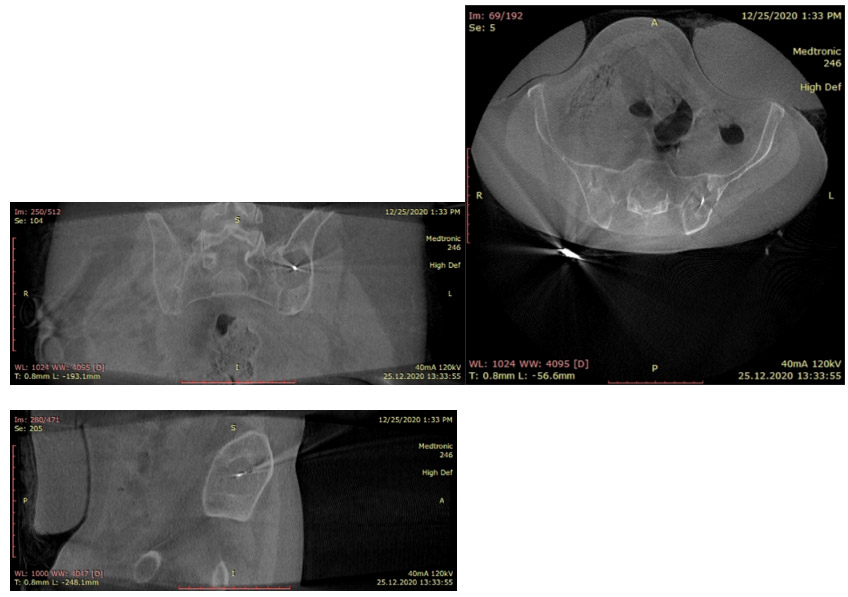

During the operation: The image shows the placement of the radiofrequency ablation probe at the metastatic focus in the left pelvic bone.